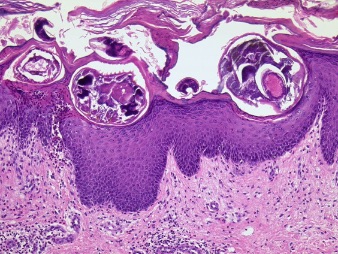

Routinehistologie bezieht sich auf die gängige Praxis der histologischen Untersuchung von Gewebeproben in der medizinischen Diagnostik. Dabei wird Gewebe, das durch Biopsien bzw. Operationen gewonnen wurde, für die mikroskopische Betrachtung vorbereitet.

Der Prozess der Routinehistologie umfasst verschiedene Schritte. Zunächst werden die Gewebeproben fixiert, um ihre strukturelle Integrität zu erhalten. Anschließend werden sie in Paraffin eingebettet, um dünne Gewebeschnitte herzustellen. Diese Schnitte werden auf Objektträger gelegt und mit speziellen Farbstoffen, wie der Hämatoxylin-Eosin-Färbung, gefärbt.

Die gefärbten Gewebeschnitte werden dann unter dem Mikroskop betrachtet und von Dermatopathologen bzw. Pathologen analysiert. Durch die Routinehistologie können verschiedene Gewebearten, Zellstrukturen und pathologische Veränderungen identifiziert werden. Dies ermöglicht die Diagnose von Krankheiten, die Beurteilung von Gewebezuständen und die Planung von Behandlungsstrategien.

Die Routinehistologie ist ein grundlegender Bestandteil der medizinischen Diagnostik und spielt eine wichtige Rolle in der Dermatologie und anderen medizinischen Fachgebieten. Sie liefert wertvolle Informationen zur Identifizierung von Krankheiten und zur Überwachung des Krankheitsverlaufs.